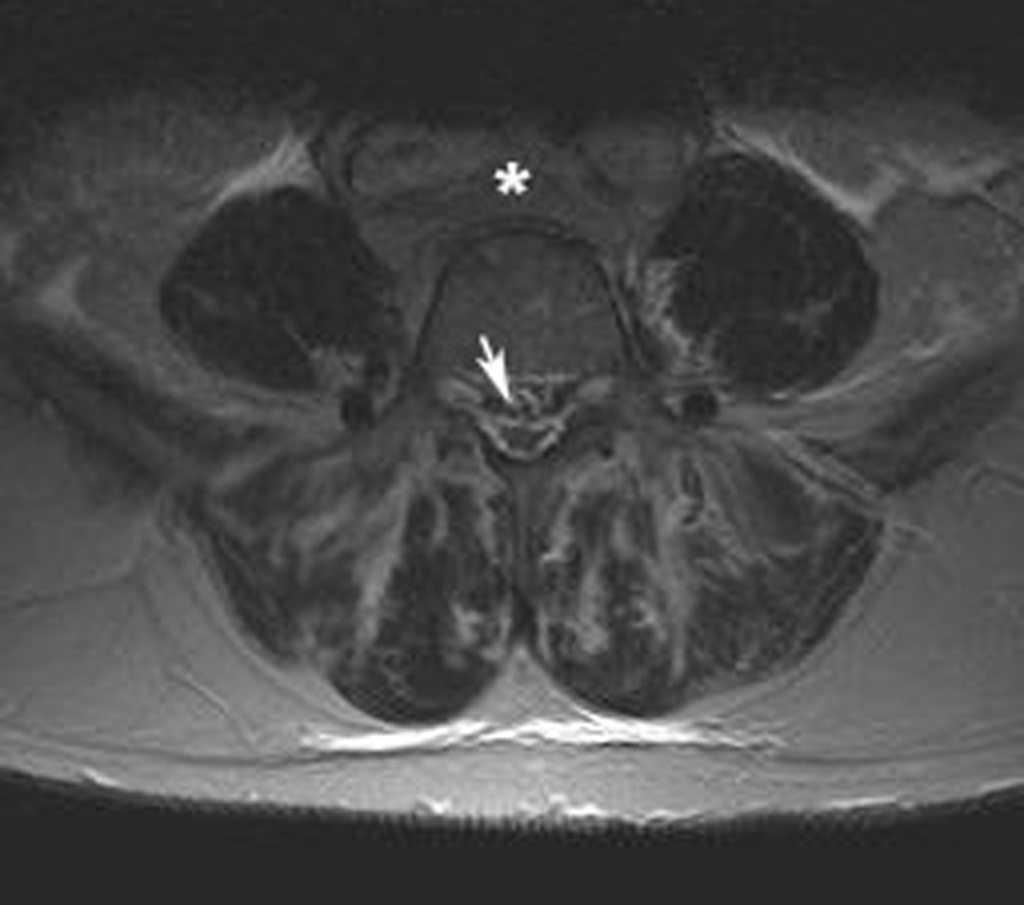

Se realizó una resonancia magnética (RM) de la columna lumbar (sin y tras contraste intravenoso) y se observaron, además de la masa retroperitoneal que comprimía la VCI, unas imágenes puntiformes y lineales hipointensas en todas las secuencias que ocupaban el espacio epidural adyacente al muro posterior de las vértebras lumbosacras, que se extendían a través de los agujeros de conjunción hacia las partes blandas perivertebrales (figs. 1-3). Esta alteración correspondía a estructuras vasculares dilatadas dependientes del plexo venoso epidural vertebral.

Fig. 1. Resonancia magnética ponderada en T1 (A) sagital línea media, (B) parasagital y (C) axial. (A) Aumento de la grasa epidural que comprime el saco tecal debido a lipomatosis (flecha); (B) imágenes hipointensas puntiformes en el espacio epidural anterior que corresponden a estructuras vasculares dilatadas del plexo lumbosacro (flechas); (C) masa retroperitoneal que engloba grandes vasos (asterisco). Se objetiva la presencia de lipomatosis (flecha blanca) y las estructuras vasculares dilatadas (punta de flecha blanca).